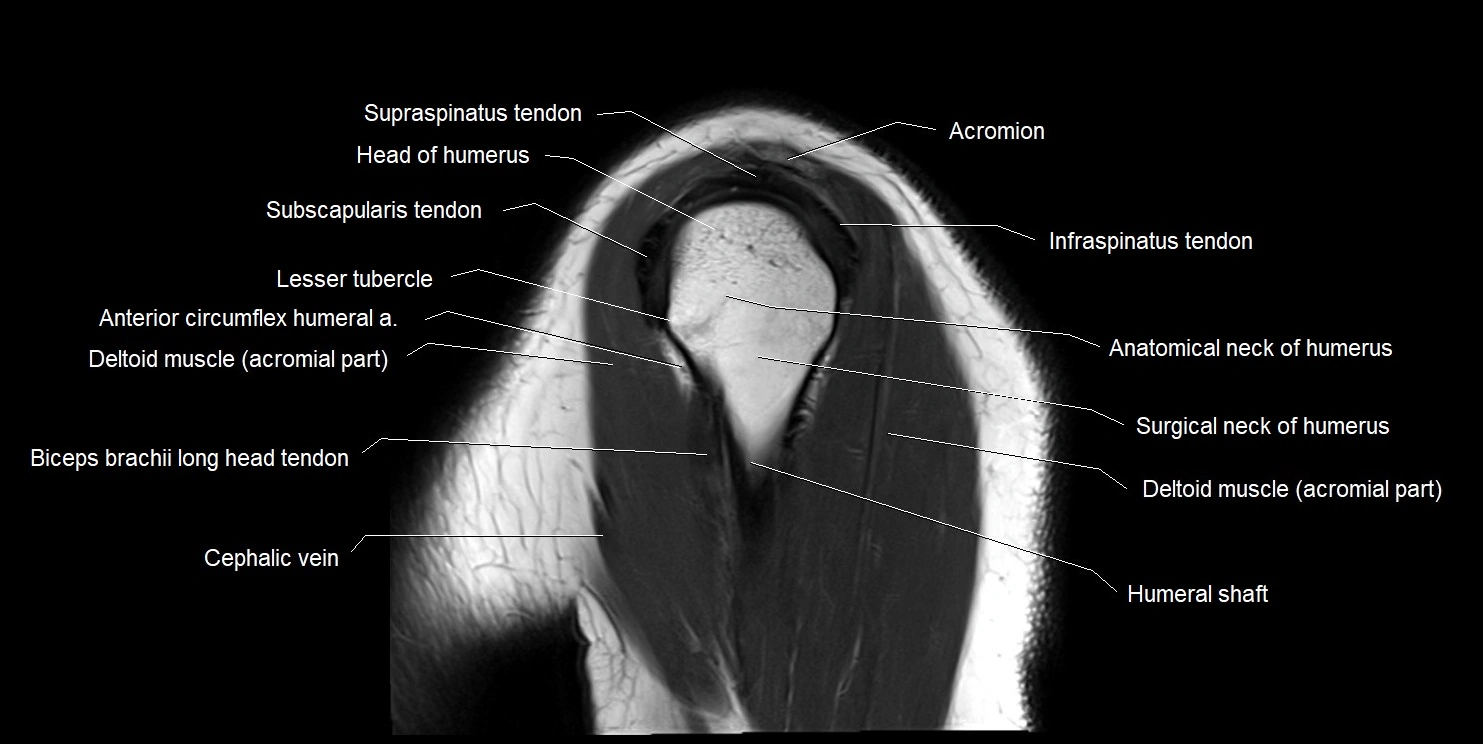

MRI images

image